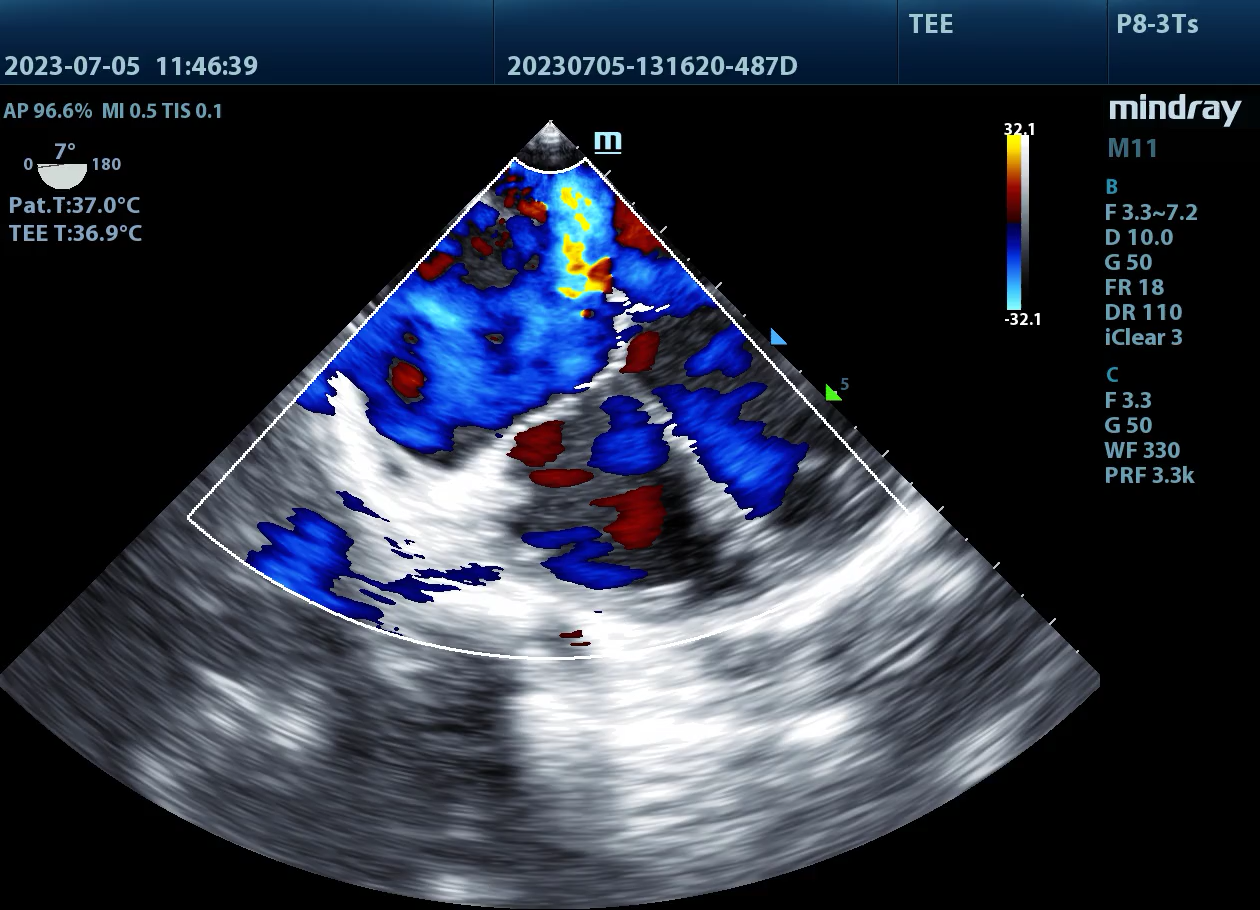

病例,小儿房间隔缺损(3),小儿经食道探头(TEE),术中监测,来源柳州市妇幼保健院东院

病例,房间隔缺损(ASD3),小儿经食道探头(TEE),术中监测,来源柳州市妇幼保健院东院